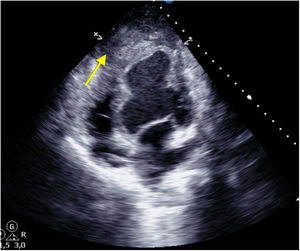

A 49-year-old male was admitted with a SCAI D cardiogenic shock following a 12-day history of non-ST-elevation acute coronary syndrome, not revascularized in his country of origin, complicated by intramyocardial dissection, resulting in a contained apical posterior hematoma (Fig. 1, yellow arrow), hemodynamic instability, and severe biventricular dysfunction requiring veno-Arterial extracorporeal membrane oxygenation (ECMO) as a bridge therapy to heart transplantation.